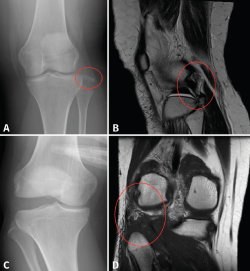

Figura 1. A: radiografía anteroposterior (AP) de rodilla, fractura-avulsión de la cabeza del peroné (círculo rojo) por lesión del complejo posterolateral (CPL); B: corte sagital de resonancia magnética del caso mostrado en la imagen A, en el que se evidencia la lesión del CPL (círculo rojo); C: radiografía AP en estrés de rodilla con bostezo al varo de grado III, por lesión del CPL; D: corte coronal de resonancia magnética del caso mostrado en la imagen C, donde se evidencia la lesión del CPL (círculo rojo).